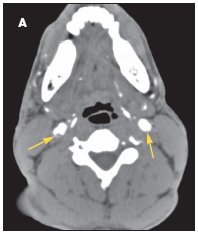

The patient was admitted with a diagnosis of stroke. A CT scan of the brain revealed no bleeding or infarction. A CT angiogram showed bilateral internal carotid dissection, on the right more than the left (A). A heparin drip and aspirin were started. MRI done 24 hours later showed acute infarction in the right basal ganglia and to a smaller degree in the right temporal lobe (B); petechial hemorrhages were noted in the acute infarction. At this point, the heparin drip and aspirin were discontinued. The patient could not be anticoagulated because of the hemorrhagic conversion.